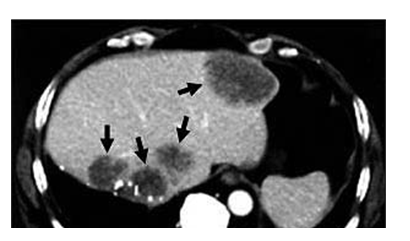

Figure 23 CT scan of the upper abdomen showing multiple metastasis in the liver of a patient with carcinoma of the large bowel (black arrow).59

A CT scan is a type of radiography that also uses X-ray, unlike the Projectional radiography the CT scan uses a higher amount of X-rays and it provides a more detailed 3D image, however in recent years, some CT scans has been developed to use a smaller amount of X-ray. The CT machine comprises of a doughnut shaped CT scanner, table, X-ray tube, X-ray detector and computer (Figure 21).54,55 The patient lie on the table before sliding into the CT scanner, the X-ray tube and camera moves round the patient at 360° to scan and produce multiple image of the internal organs of the body, depending on the organ of interest a contrast material might be administered either through the mouth, rectum or injected into the vein to highlight the scanned organ.55 The scan is performed in a separate computer room where the images are displayed and the technologist communicates with the patient with the aid of speakers and microphones.56 The major advantage of CT scan is rapid acquisition of clearer diagnostic images of a wider proportion of the body.56,57